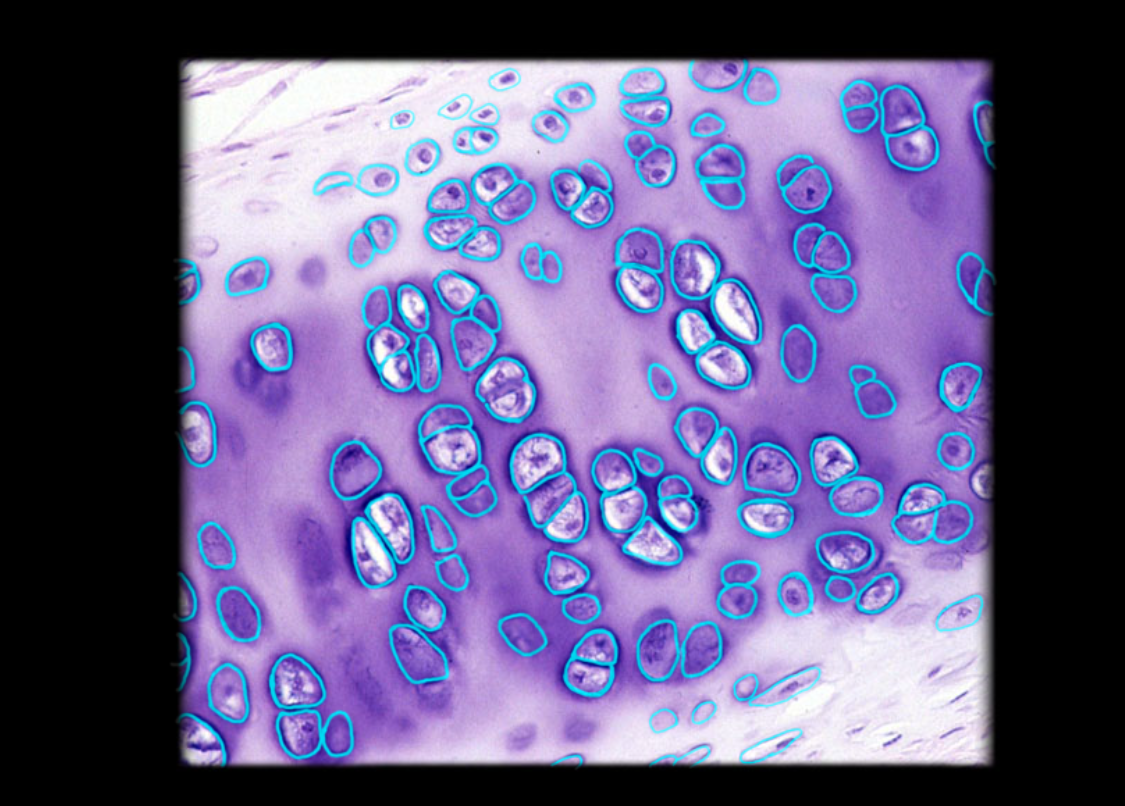

Lacuna (with chondrocyte) in hyaline cartilage

15

New cards

Chondrocyte (in lacuna) in hyaline cartilage